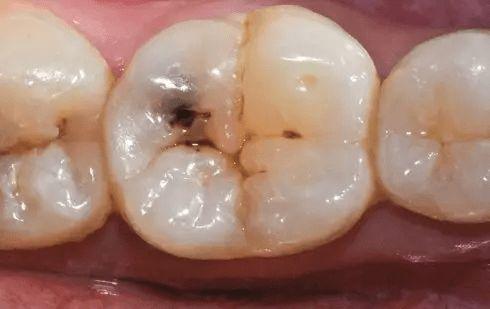

齲齒是一種常見的口腔疾病,不僅會給患者帶來疼痛和不適,還可能影響咀嚼、發(fā)音和美觀。預防齲齒至關(guān)重要,而一旦患上齲齒,及時有效的治療也是必不可少的。下面讓我們深入探討這兩個關(guān)鍵方面。

2.填充治療

(1)治療過程:去除齲壞組織,制備洞形,選擇合適的充填材料(如銀汞合金、復合樹脂、玻璃離子等)進行填充,恢復牙齒的外形和功能。

(2)效果:填充治療是目前治療齲齒最常用的方法,成功率較高。一項對1000例填充治療病例的跟蹤研究發(fā)現(xiàn),治療后5年內(nèi)的成功率可達90%以上。